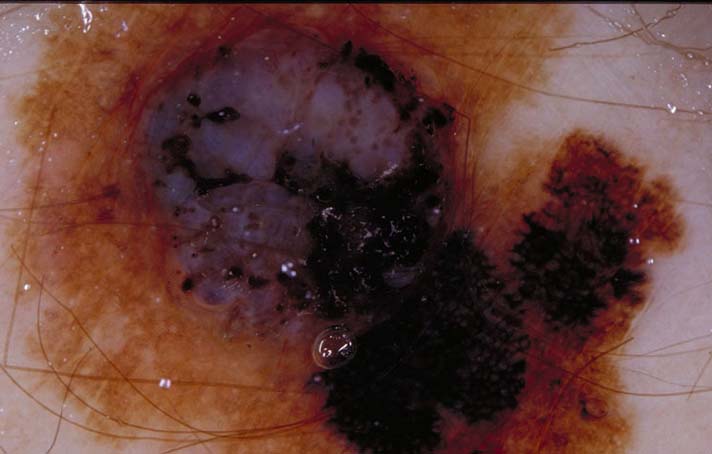

| 120 "diagnosis.char"="Melanocytic lesion" "comment.char"="" "features.char"="Aggregated brown or black globules|Pigment network - pseudonetwork (see exception 1)|Pseudopods or Radial Streaming (circumferential or focally present)" | "diagnosis.char"="Invasive Melanoma, Breslow 0.8mm" "breslow_depth.float"="0.8" "comment.char"="" "features.char"="Blue-white veil|Broadened network|Multiple (5-6) colors|Peripheral black dots/globules|Pseudopods" |  |  |